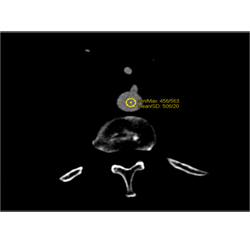

Example of User Bolus Triggering for Evaluation of the Pancreas With Dual Source CT